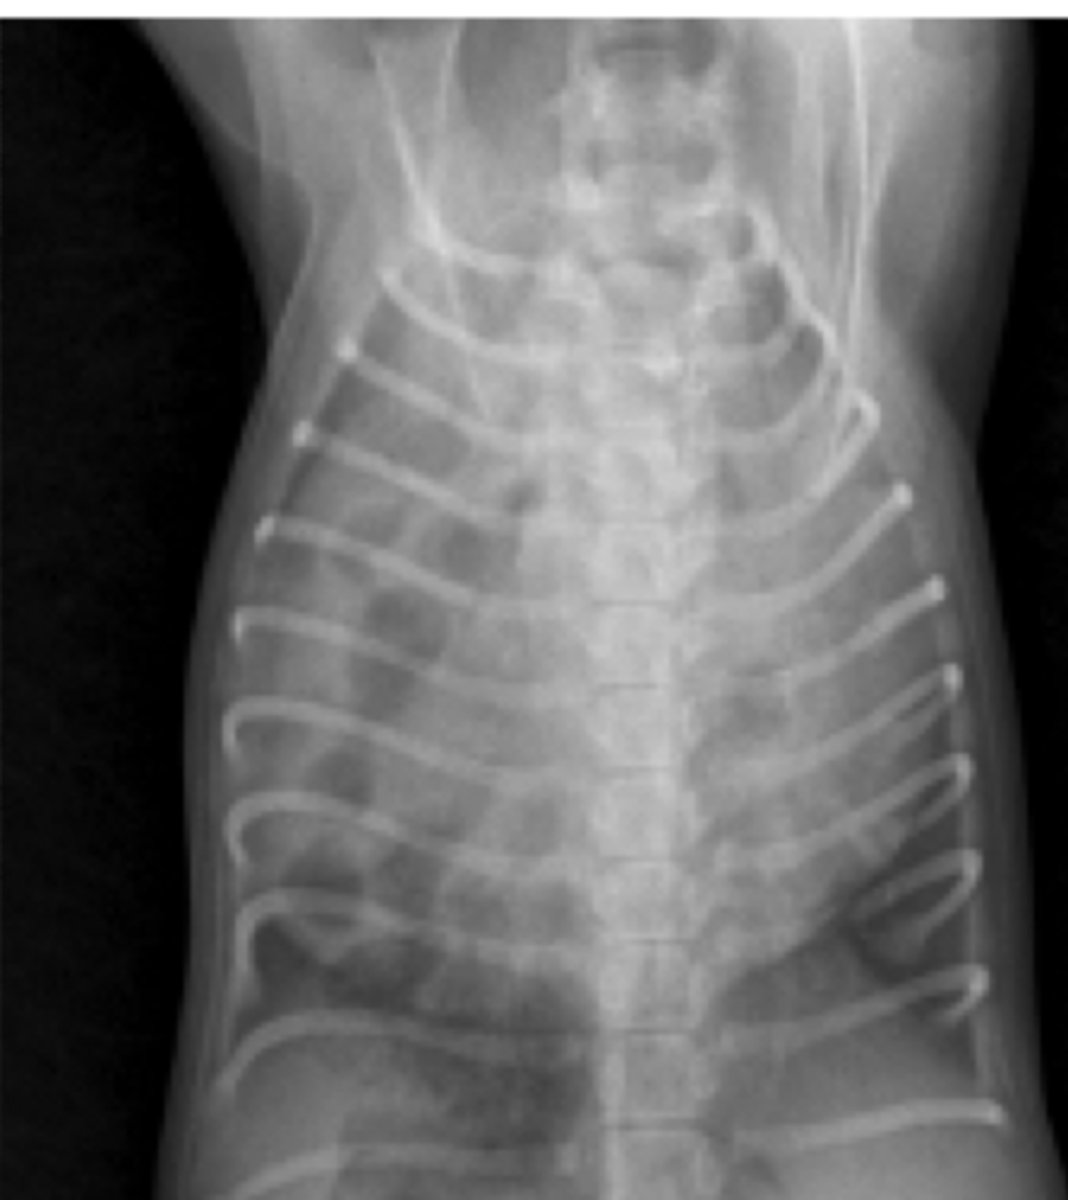

- liquido/ ascitis

- animal joven

¿qué son las causas de pérdida de definición abdominal en una radiografía?